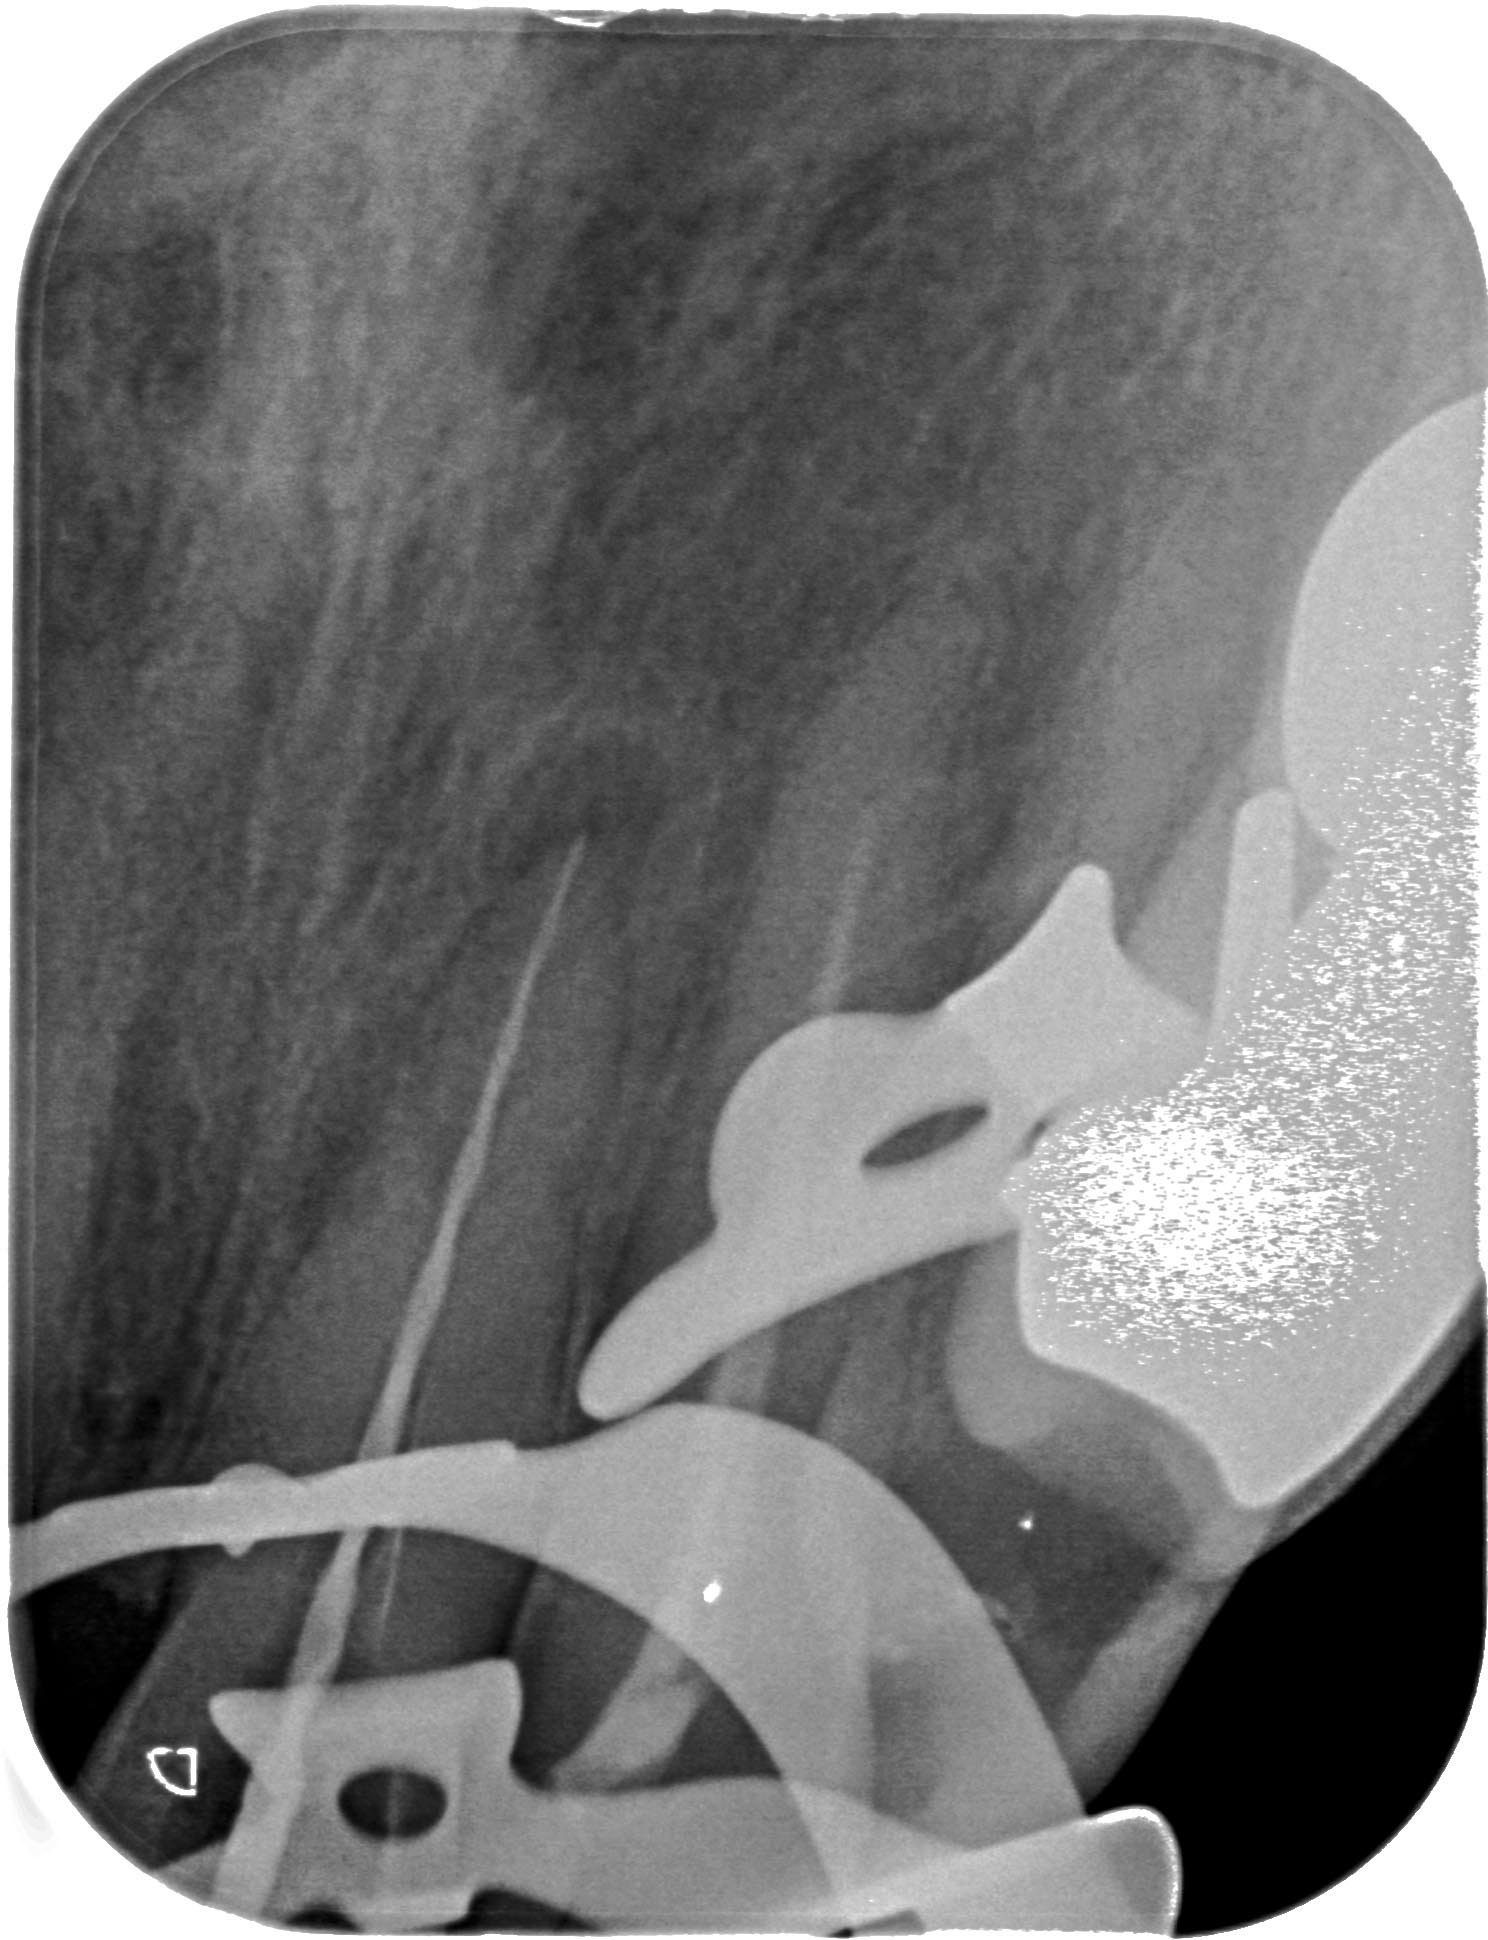

KC_21 (1 von 1)-2 Veröffentlicht 21. Januar 2016 am 1488 × 1940 in Seitenkanal – Dejavu 21 Röntgenmessaufnahme